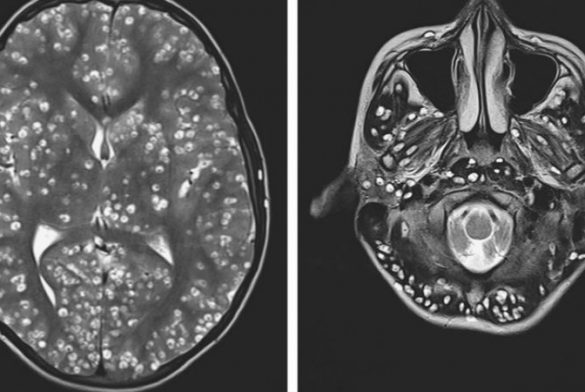

28 marzo, 2019 ¡Ojo con lo que comes! Joven murió por larvas que invadieron su cerebro tras consumir cerdo mal cocinado El caso de un joven que falleció por comer cerdo mal cocinado, ha dado la vuelta al mundo y ha visibilizado los peligros de la cisticercosis, una infección